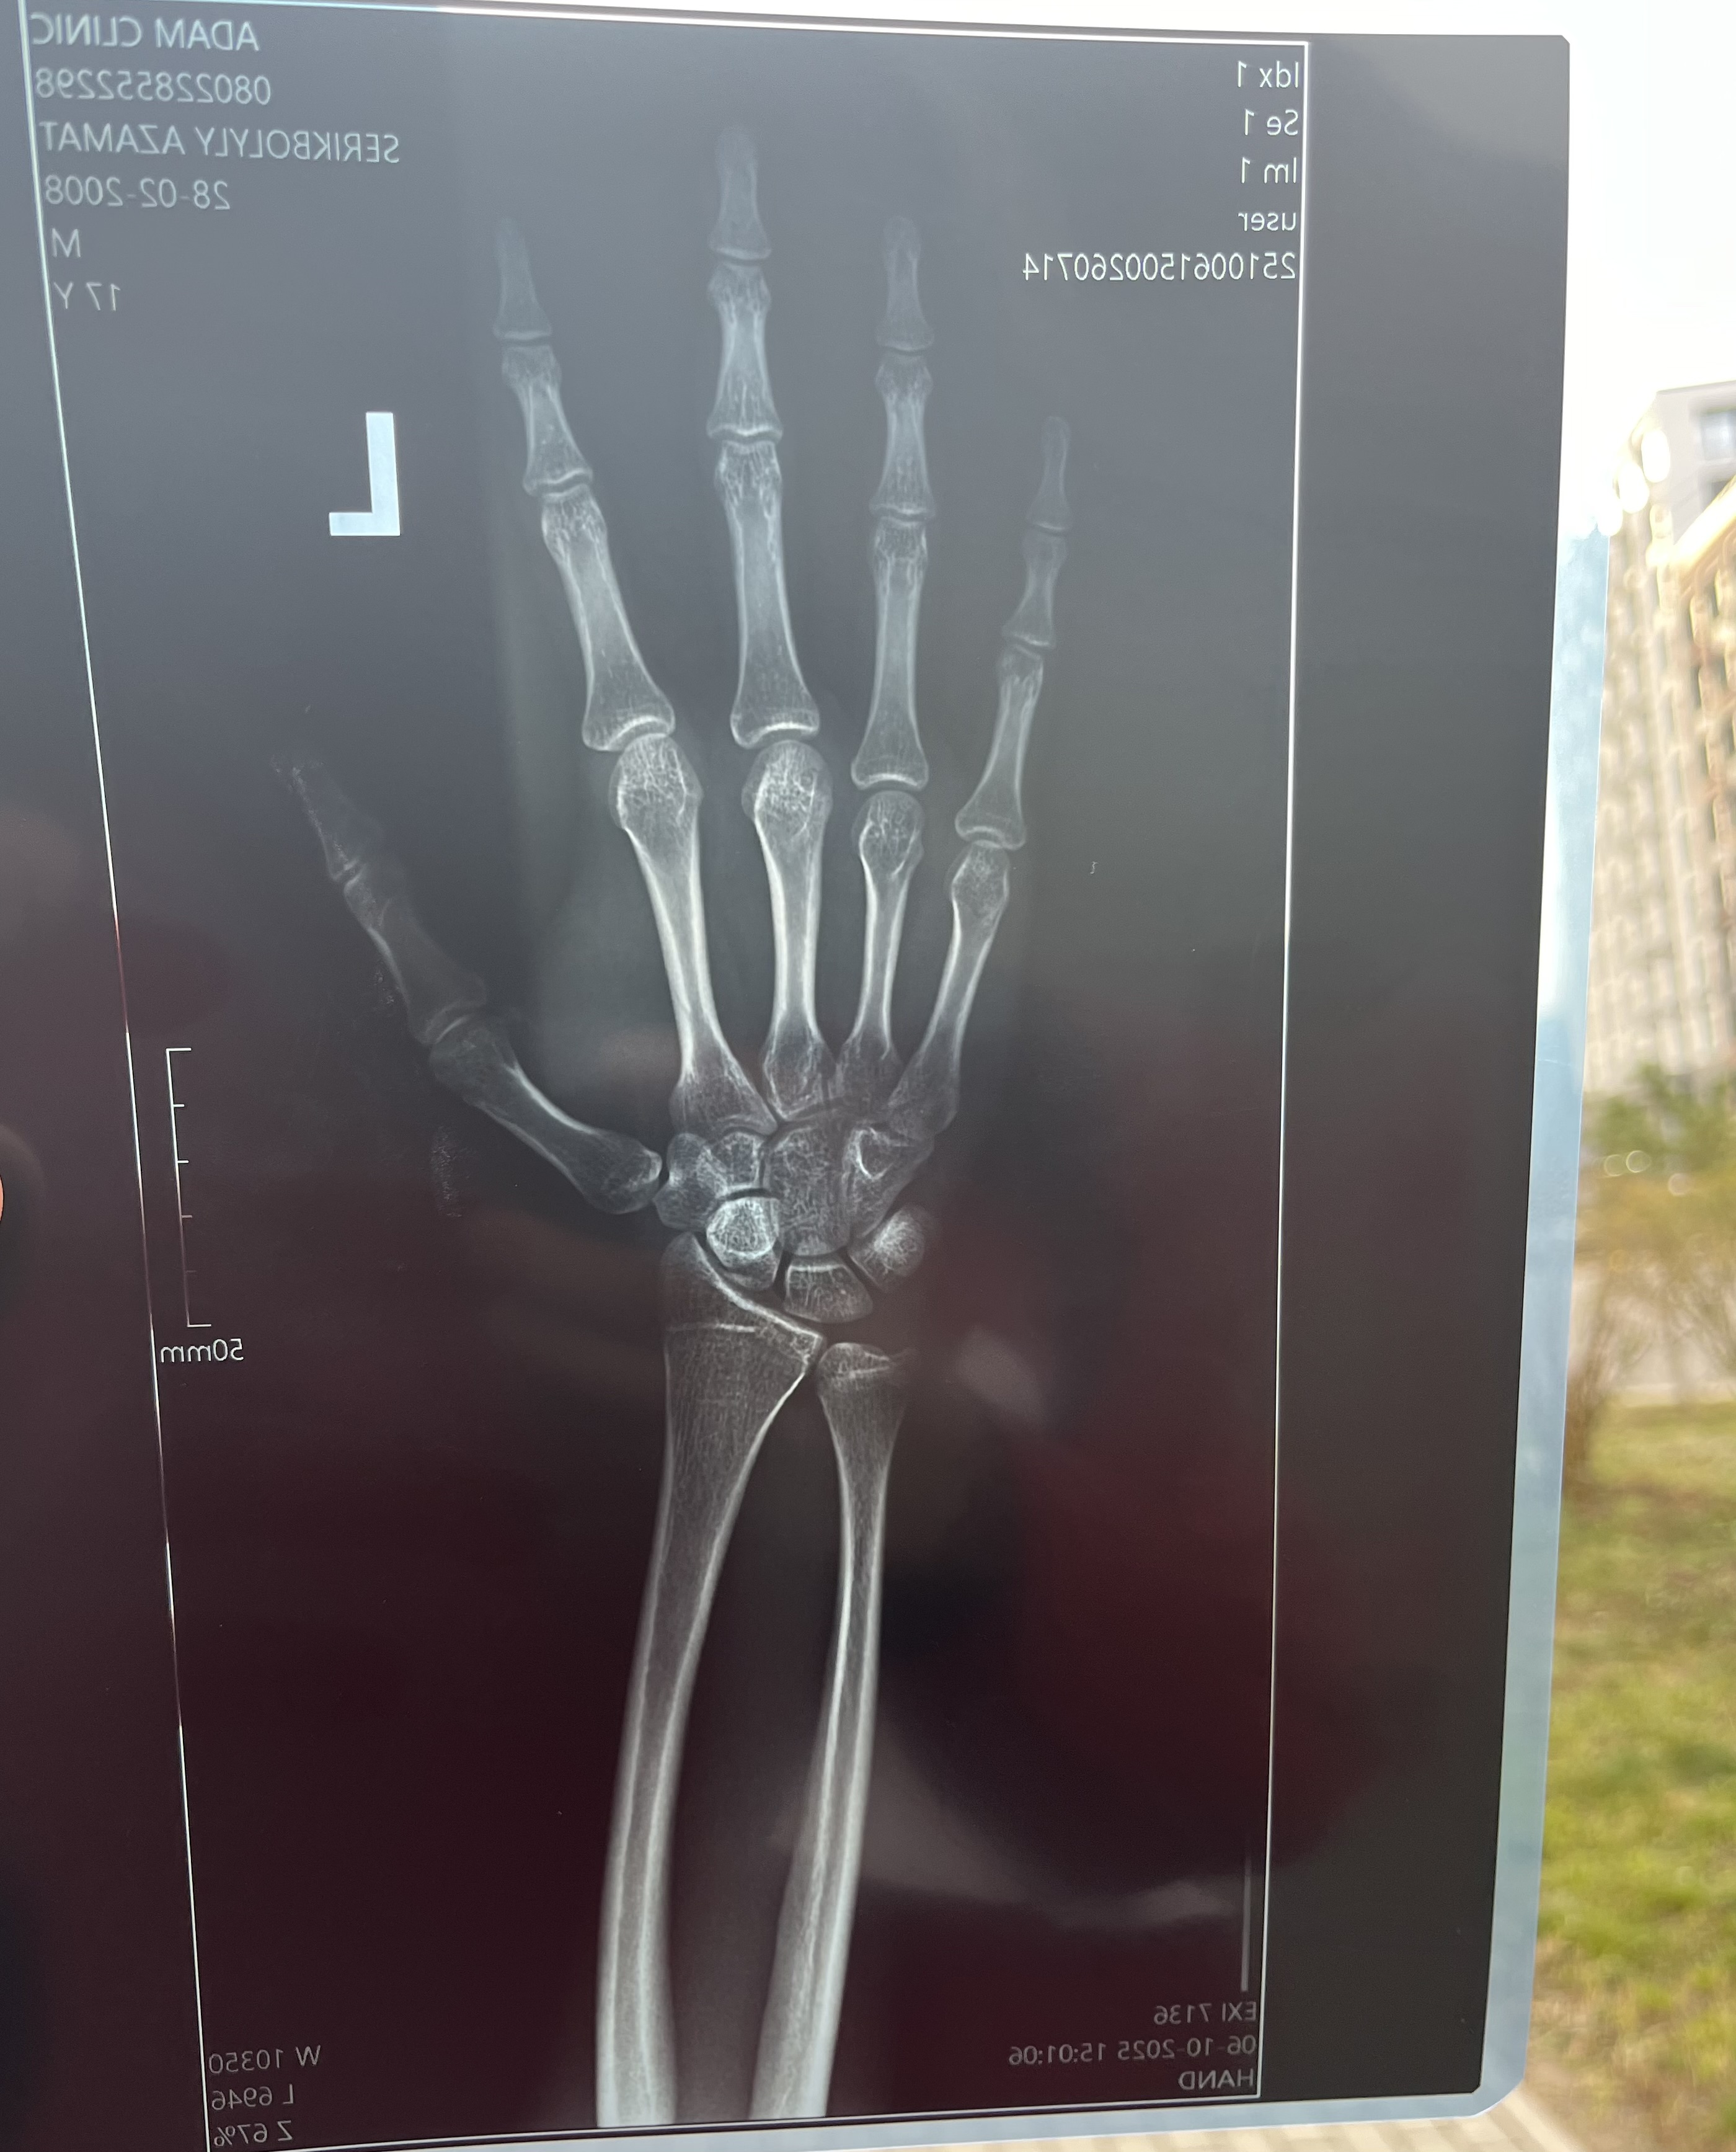

Are my growth plates closed?wrist xray, 183 17

He didn’t tell me anything, i think he just does the xray but cant consult, I was hoping they are open

duh he didnt, cuase he prolly isnt specialized in the matter. you should prolly speak to a development expert of an auxologist